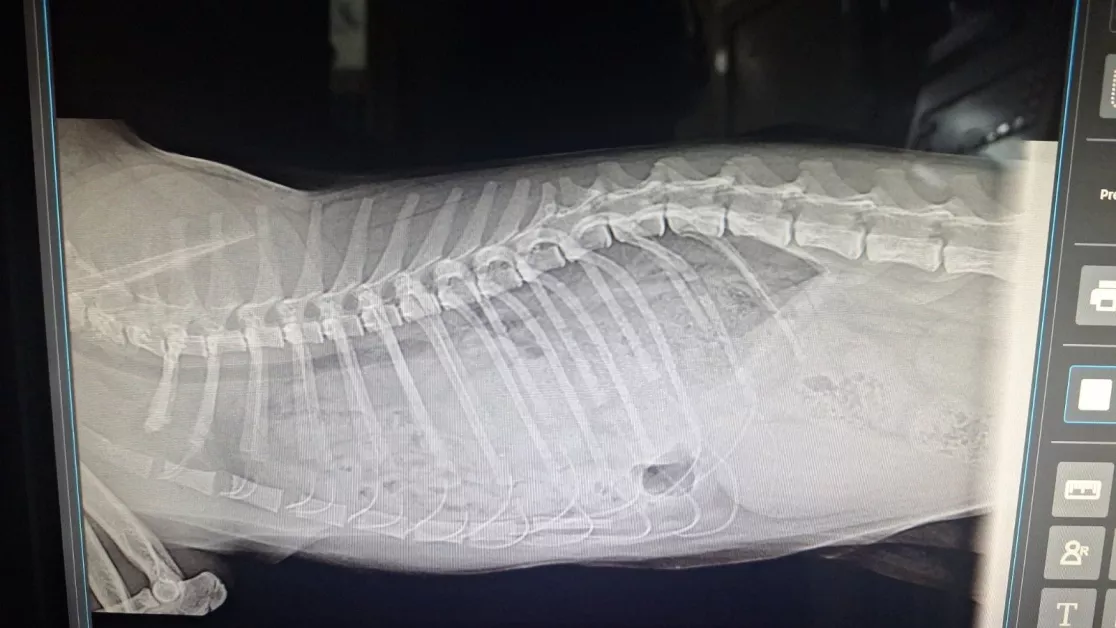

„Кову се появи при нашата котешка колония като социален и гальовен младеж, търсещ човешка близост — всичко показва, че някой някога го е обичал… и после го е изоставил“, споделят доброволците от фондацията. Преди дни забелязали, че котето диша учестено и тежко, след което веднага го закарали в клиника. Там диагнозата потвърдила страховете им: „Две тежки диафрагмални хернии. Органите му са се преместили в гръдния кош и притискат дробовете и сърцето му. Налага се спешна операция, защото в противен случай Кову има много голяма опасност да се задуши“, обясниха от „Втори живот“.